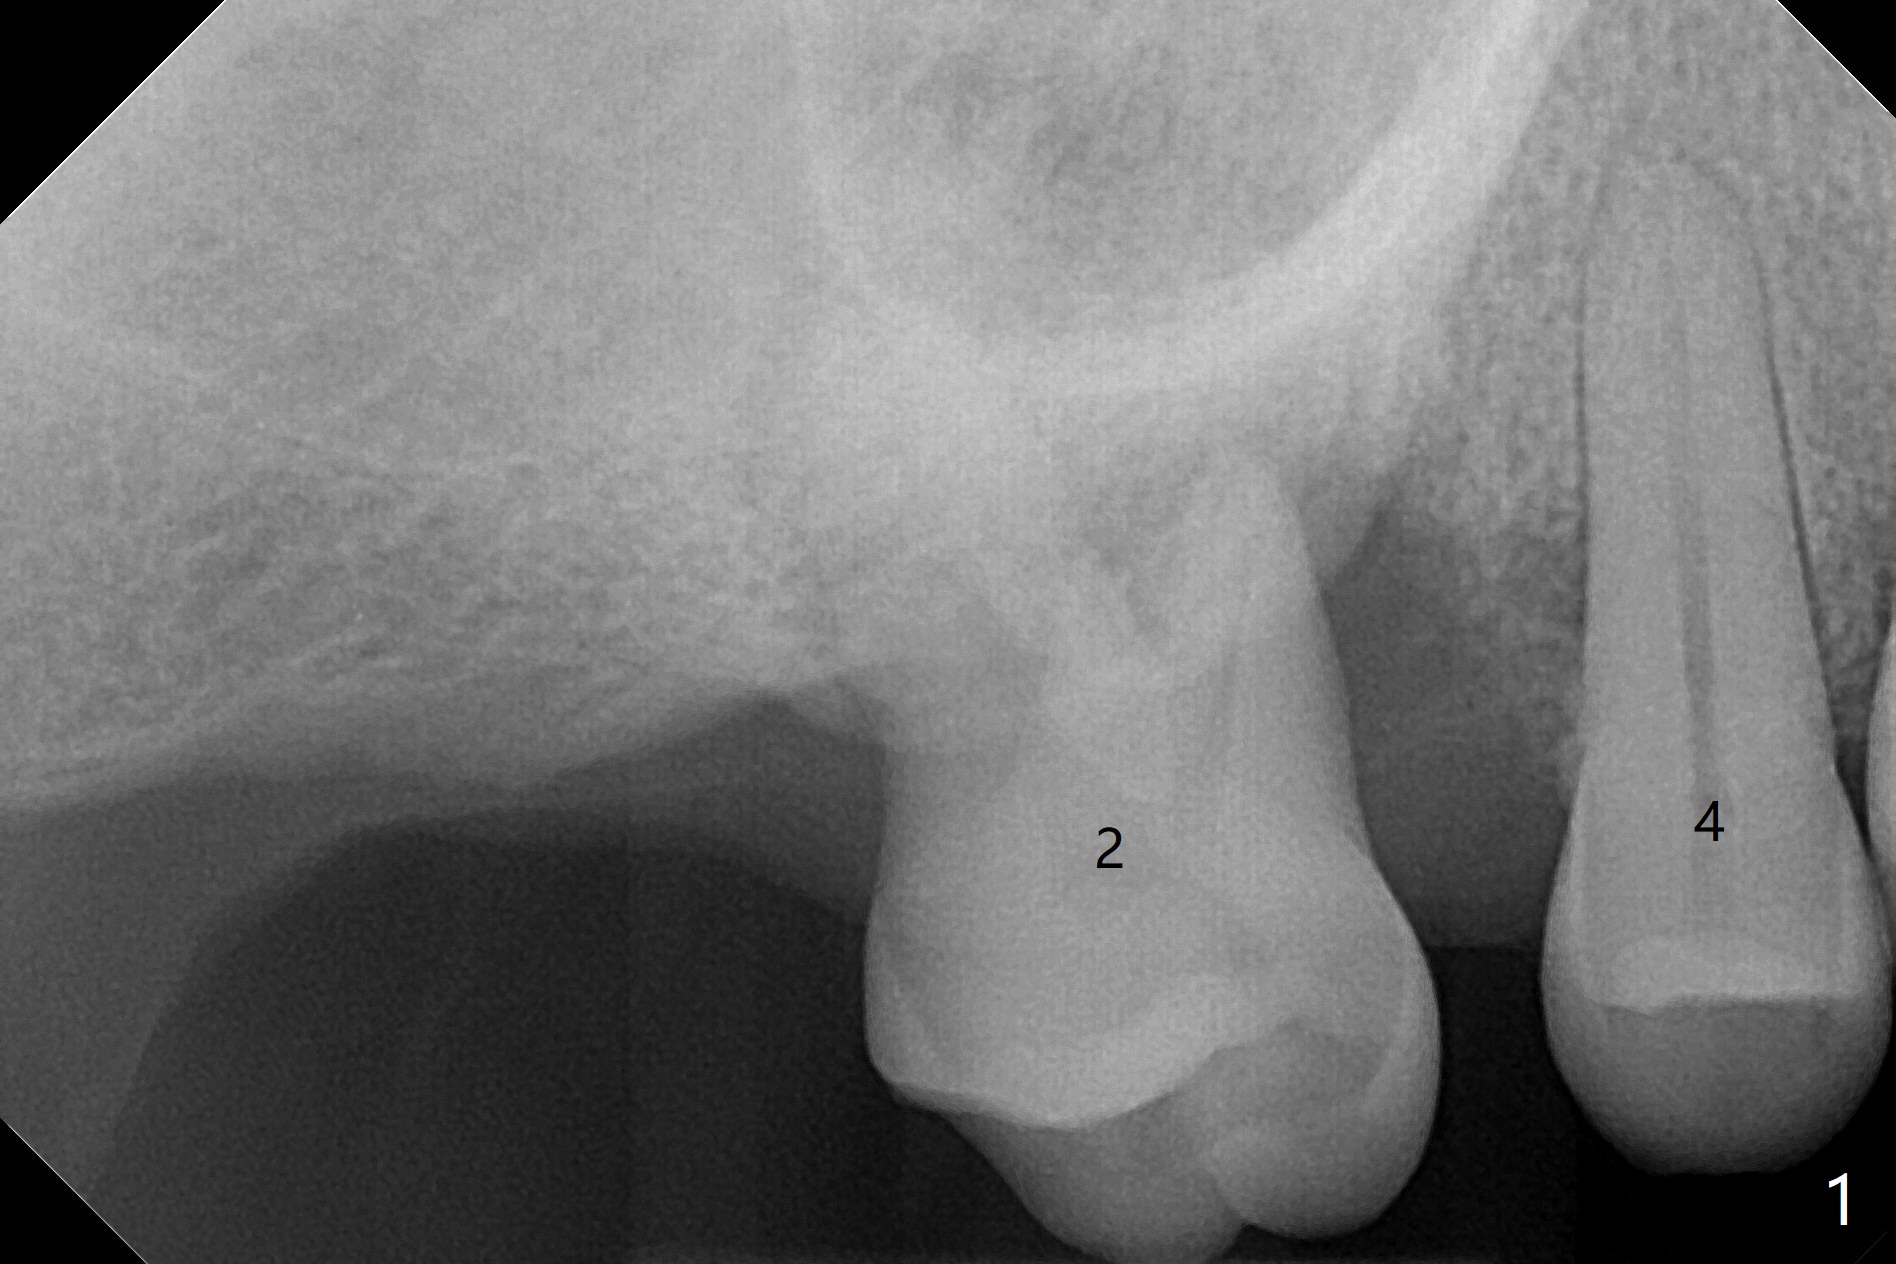

牙周敷料与缝线粘连

66岁男要求拔除2号牙(近中倾斜,3号牙缺失,图一),术中发现巨大骨质缺损,病人同意植骨(皮质骨,用血调袢,图二:*),覆盖Cytoplast,使用PTFE缝线,8字形缝合,两次。之后牙周敷料覆盖。术后十二天,敷料松动,但是不脱落,因为敷料与缝线粘连,牙龈好像已经固定不可吸收膜,不得不撤除缝线(图三)。Return to Protect Graft 下一个不使用敷料病例 位点保存 Xin Wei, DDS, PhD, MS 1st edition 06/12/2021, last revision 07/03/2021